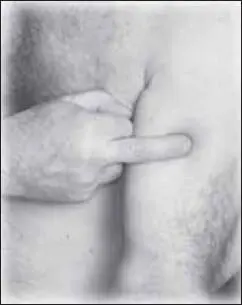

Начинаем с точки тянъ-ту (расположена в яремной выемке грудины, в ее центре, на передней поверхности шеи) (рис. 122).

Следующая точка – цзы-гун (расположена на средней линии грудной клетки на уровне 3-го ребра) (рис. 123).